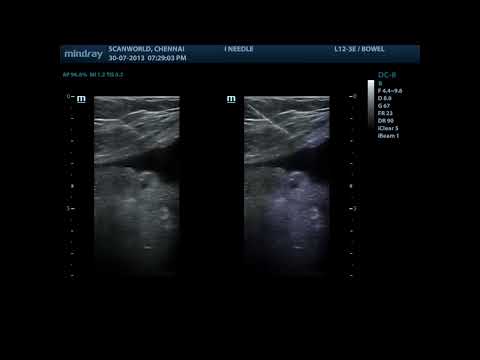

iNeedle

Функция iNeedle (улучшения визуализации иглы) использует дополнительный наклонный ультразвуковой луч, перпендикулярный направлению иглы, при этом основной УЗ поток лучей (перпендикулярный рабочей поверхности датчика) также сохраняется. Пользователь может произвольно регулировать угол наклона.